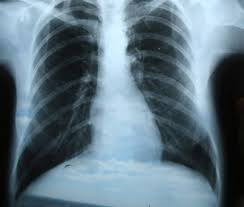

Tomografia e ressonância magnética são exames de imagem bastante detalhados, que servem para analisar com precisão coração, vasos sanguíneos, pulmões, cérebro e ossos. Se você ainda nunca fez, talvez um dia precise – por isso, é sempre bom saber como eles funcionam.

A tomografia, assim como o raio X, também usa radiação. Mas o contraste não é radioativo. No caso da cintilografia, o contraste é um remédio que contém radioatividade. Mas não há risco de câncer, porque as exposições costumam ser bem pontuais